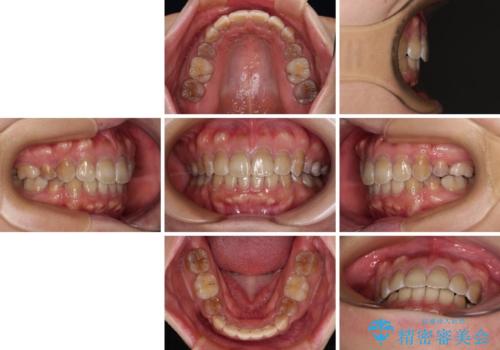

横顔の印象が大きく変わる ワイヤー装置での抜歯矯正

- 審美装置

- 2年6ヶ月

- 口元の突出感を気にして来院された患者様です。

上下前歯が著しく前突している状態であったので、上下左右の第1小臼歯4本を抜歯し、ワイヤー装置にて矯正治療を行うこととしました。

舌の突出癖により、前突になったと考えられたため、舌のトレーニングをしっかりと行うよう指導しました。

4本の歯を抜歯したことで、飛び出していた口元が引っ込み、横顔が大きく改善されました。